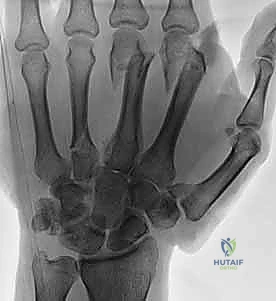

معرض الصور الشعاعية: تقييم النتائج الجراحية (Post-Op X-rays)

النجاح الحقيقي يُقاس بالاستعادة المثالية للشكل التشريحي للعظم. توضح هذه الصور الشعاعية بعد الجراحة الدقة المتناهية في إعادة محاذاة العظام وتثبيتها.

التثبيت المحكم يسمح بالشفاء العظمي الأولي (Primary Bone Healing) دون تكوين كتلة عظمية كبيرة (Callus) قد تعيق حركة الأوتار المنزلقة فوقها.